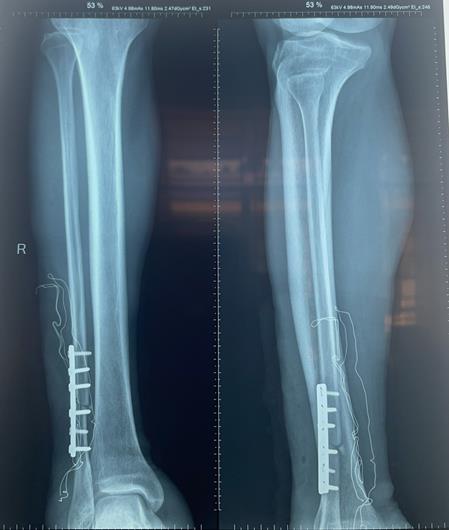

Hình ảnh chụp X-Quang chân phải của bệnh nhân trước (ảnh 1) và sau phẫu thuật kết hợp xương (ảnh 2)

Các bác sĩ chuyên khoa chấn thương chỉnh hình của Trung tâm đã phối hợp với các bác sĩ chuyên khoa gây mê hồi sức để thực hiện ca phẫu thuật kết hợp xương. Sau phẫu thuật, vùng cẳng chân phải của bệnh nhân đã vận động được. Đến nay, bệnh nhân đã được xuất viện.